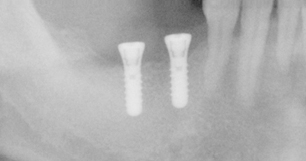

インプラントとは、虫歯や歯周病、事故などで失った自分の歯の部分に、入れ歯やブリッジを使わず、人工の歯根をあごの骨に埋め込み歯を作る治療法です(※要手術)。

インプラントは、この2つの方法の足りない部分を補う方法です。

固定式であるため、ガタついたりせず、自分の歯のように強くかめるようになる人気の治療がインプラントです。